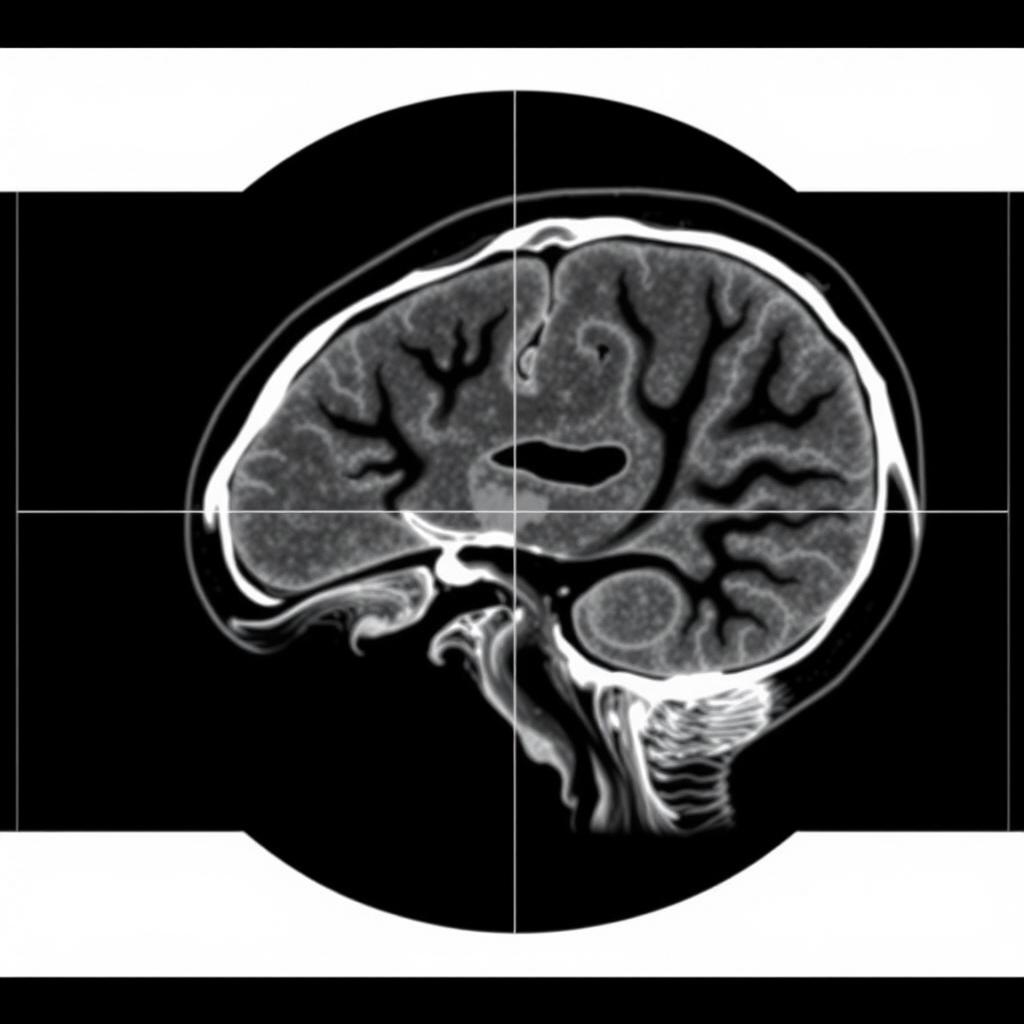

이 임상 2상 시험은 유도성 비호지킨 림프종 환자를 대상으로 표준 방사선 치료와 저용량 방사선 치료의 안전성과 효과를 비교합니다. 표준 방사선 치료는 보통 12회에 걸쳐 시행되며, 효과는 뛰어나지만 독성 위험이 높습니다. 방사선 치료는 고에너지 X-레이, 입자 또는 방사성 씨앗을 이용해 암세포를 파괴하는 방법이며, 용량 조절이 핵심입니다. 따라서 독성을 줄이면서 충분한 항암 효과를 낼 최적 용량을 찾는 것이 중요한 과제입니다.